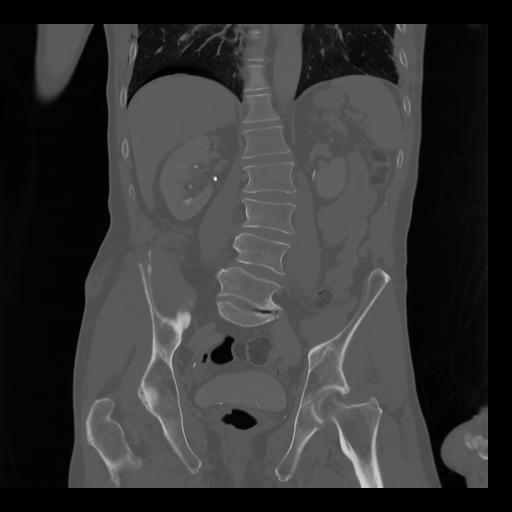

35 CUERPO,CE,Coronal,3.000,CUERPO,Coronal,